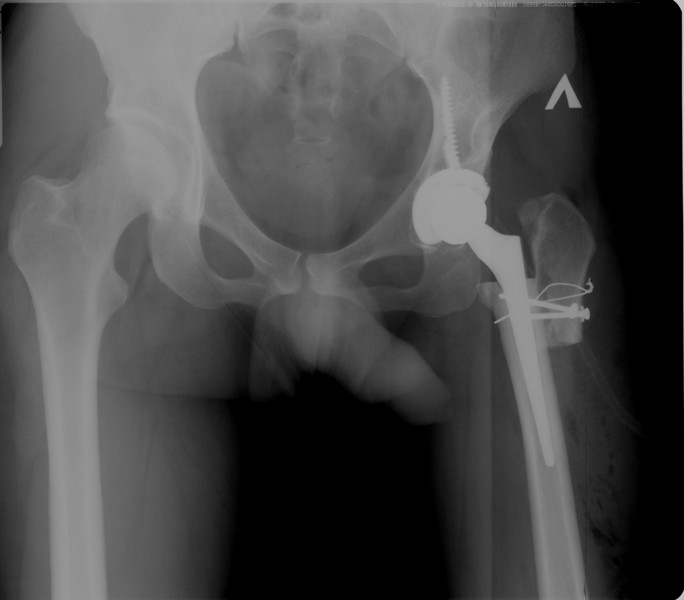

Рентгеновские снимки: Синовит тазобедренного сустава